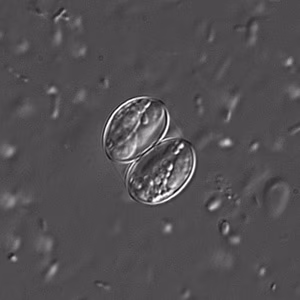

Both sporulated oocysts (containing two sporocysts) and individual sporocysts can be passed in stool

. Sporocysts contain four sporozoites and a refractile residual body. Sporocysts ingested by the intermediate host (cattle for S. hominis and pigs for S. suihominis) rupture, releasing sporozoites. Sporozoites enter endothelial cells of blood vessels and undergo schizogony, resulting in first-generation schizonts. Merozoites derived from the first-generation invade small capillaries and blood vessels, becoming second-generation schizonts. The second generation merozoites invade muscle cells and develop into sarcocysts containing bradyzoites, which are the infective stage for the definitive host

Sarcocystis oocysts in wet mounts.

Sarcocystis oocysts in wet mounts viewed under differential interference contrast (DIC).

For intestinal sarcocystosis caused by S. hominis and S. suihominis, diagnosis is made by the observation of oocysts or sporocysts in stool. They are easily overlooked as they are often shed in small numbers. Also, the two species cannot be separated by oocyst or sporocyst morphology. When humans serve as dead-end hosts for non-human Sarcocystis spp., diagnosis is made by the finding of sarcocysts in tissue specimens.